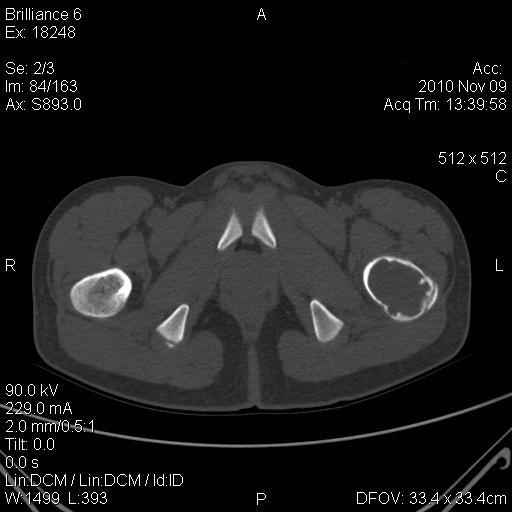

Мальчик 13 лет. В течение нескольких месяцев беспокоят боли в левом тазобедренном суставе.

При обследовании выявлена киста шейки левого бедра с сопутствующими изменениями в головке бедра, которые мы трактуем как дистрофические. Планируем вскрытие и санацию полости кисты передне-боковым доступом, костную пластику. Перед нами возникли следующие вопросы: для пластики использовать крыло подвздошной кости либо большеберцовую кость,либо их комбинацию, (полость большая,одним крылом можно не обойтись) или донорский аллотрансплантат с Коллапаном? Фиксировать ли? Если фиксировать, то чем? Доступны обычные угловые пластины либо АВФ.

Ув. Сергей! Д-з: или солитарная киста, или аневризмальная (есть небольшое "вздутие") или остеобластома ( старое название "остеобластокластома"). Если 3 вариант то полость надо обработать спиртом или азотом. Предпочтительнее аутопластика из 2 подвздошных костей. Так как срок фикс. длительный то АВФ субоптимален. Предпочтительнее фиксация угловой нестандартной пластиной 110-115 град ("разогнутая" 95 град).В запасе минимум 3 пластины с 3 типоразмерами клинка (расстояние от tuberc. innominatum до перехода метаэпифиза в нижний полюс головки).Ножка: минимум 3 винта в "здоровой" кости диафиза.Перед формированием канала пробойником 3 "страховочные" спицы: большой вертел центр головки (межвертельный перелом лучше перелома шейки) Аутопластика после МОС.